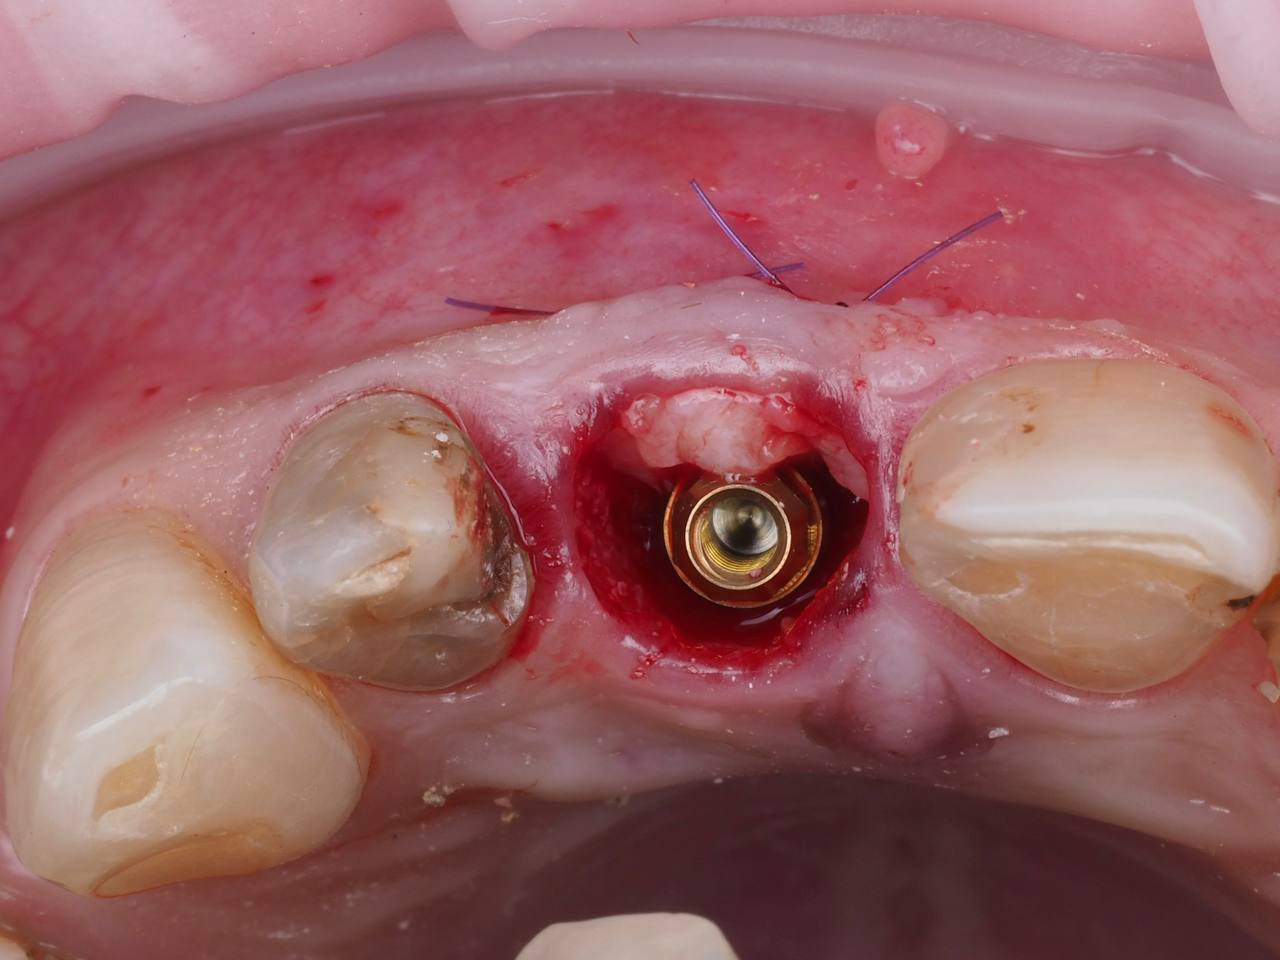

Одномоментная имплантация 1.1

AnyRidge, мультиюнит Octa, CCT, временная коронка